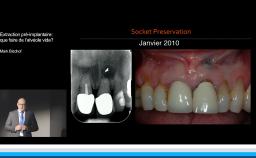

Choix chirurgicaux, incidences biologiques

La présentation du Dr Rousseau reprend les choix auxquels est confronté le chirurgien-dentiste lors de la mise en place d’un implant dentaire.

De l’incision jusqu’aux sutures, le praticien fait face à une multitude d’options thérapeutiques qui conditionne la survie voire le succès de l’implant. La plupart des choix chirurgicaux repose sur la bonne compréhension des mécanismes biologiques de la cicatrisation et de l’homéostasie. Comprendre ces mécanismes, c’est orienter ses choix chirurgicaux vers un exercice raisonné de l’implantologie et accroître ses chances de succès.